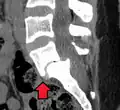

Anterolistesis L5/S1 -

Anterolistesis L5/S1. Flecha azul pars interarticularis normal. La flecha roja es una ruptura en pars interarticularis -

Anterolistesis L5/S1